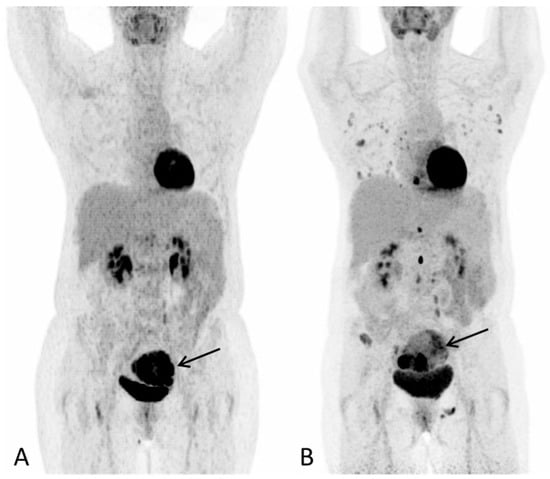

Figure 1. A 57-year-old post-menopausal woman underwent gynecological examination due to intermittent vaginal bleeding over the course of one month with no other symptoms. On transvaginal ultrasound, a tumor thought to represent a leiomyoma was reported. A subsequent hysteroscopy showed the uterine cavity to be filled with soft necrotic tissue, suspected to derive from a leiomyoma. However, histological examination depicted hepatoid adenocarcinoma. At the time of diagnosis, the laboratory work-up for tumor markers showed S-AFP 110610 (ref: <12 kIU/L), Ca-125 13 (ref: <35 kU/L), CA 19-9 17 (ref: <37 kU/L) and CEA 4 (ref: <5µg/L). 18F-FDG PET/CT was performed for staging purposes. (A) PET Maximum intensity projection (MIP) baseline scan and (B) PET MIP evaluation scan after three series of chemotherapy (paclitaxel and carboplatin) showed progression with multiple new metabolic active lesions in the lungs, bones and lymph nodes. The primary tumour in the uterus is seen with increasing inhomogeneous metabolic activity, with areas of low metabolic activity indicating necrosis ((A,B), arrow). Notably, there were no FDG-avid lesions in the liver on either scan. S-AFP had risen to 258,900 IU/L. Due to progression, the treatment plan changed to sorafenib, which is one of the few systemic treatment options available for advanced HCC.